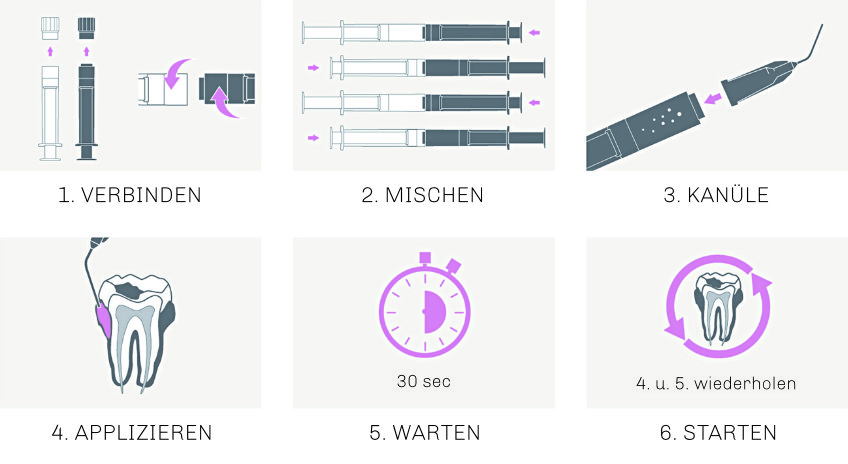

Vor Gebrauch werden beide Komponenten miteinander gemischt:

PERISOLV® zeichnet sich durch seine einfache Anwendung (schnelle Vorbereitung & kurze Einwirkzeit) aus.

EINFACHE ANWENDUNG

Schnelle Vorbereitung und kurze Einwirkzeit